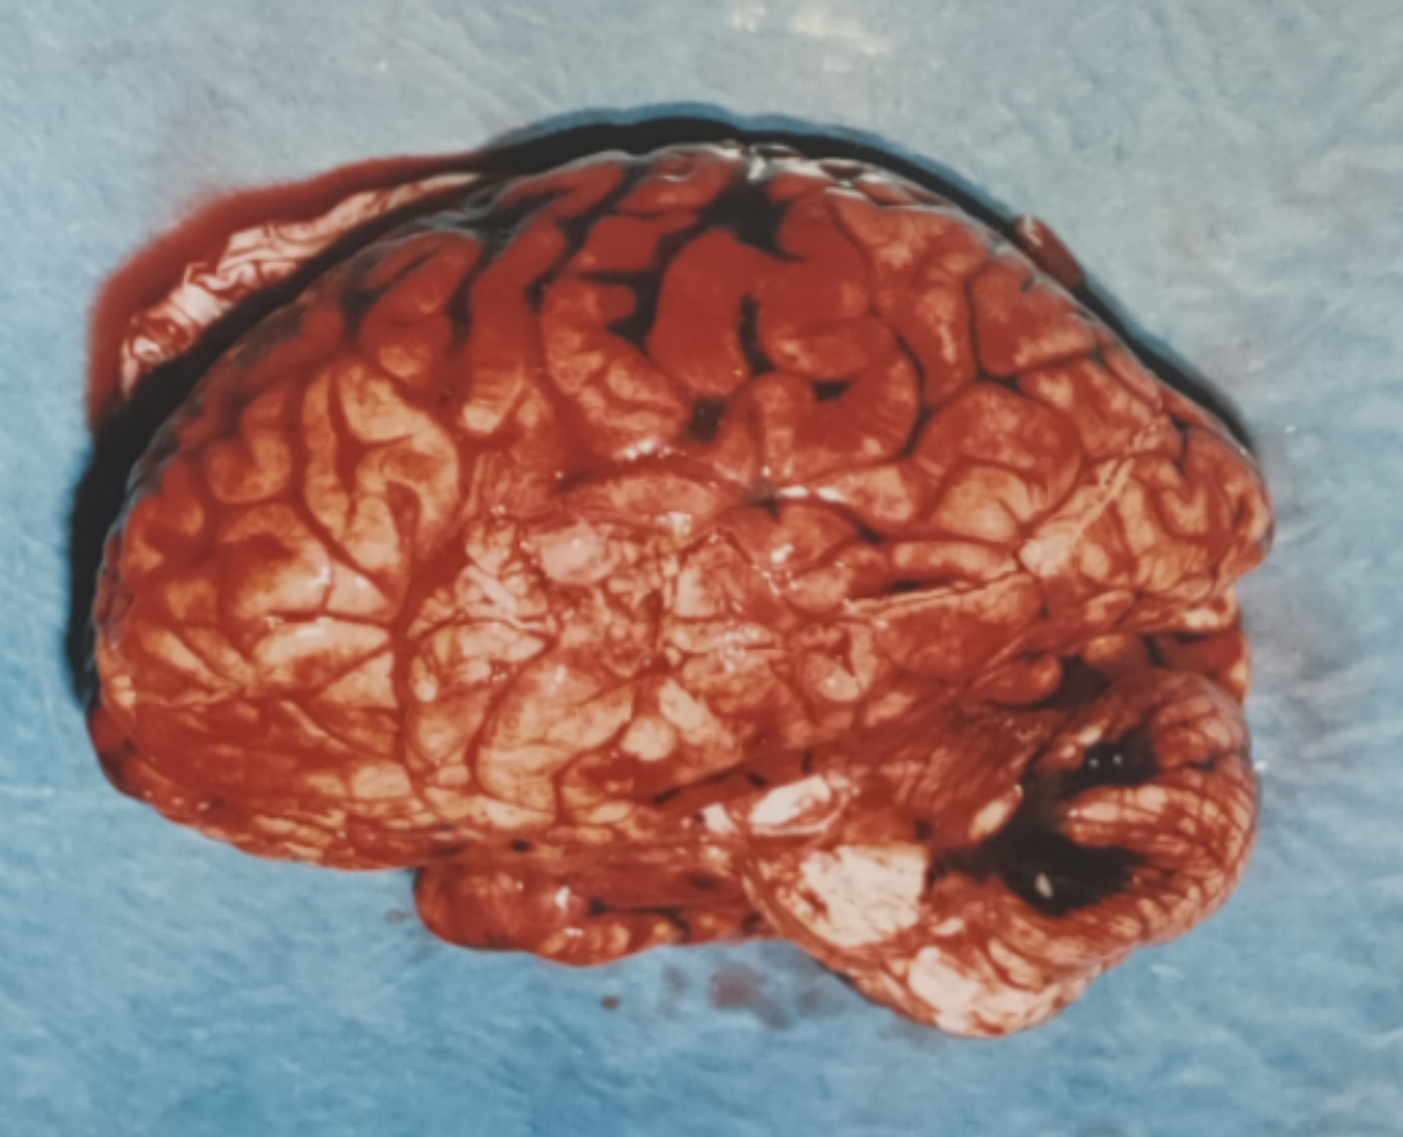

今天来讲讲上面那个脑子的事

那些黑色的部分都是脑外伤引起的蛛网膜下腔出血,程度不算重,顶多是个轻伤二级( ゚∀。)

要命的是第一张图正中间的部分那两个圆形的小黑点,第二张图对应的位置可以看到脑组织的星芒状绽裂

尸检倒是简单,脑子都成那样了还有啥可说的( ゚∀。)

解剖意见:枪击致重度颅脑损伤死亡